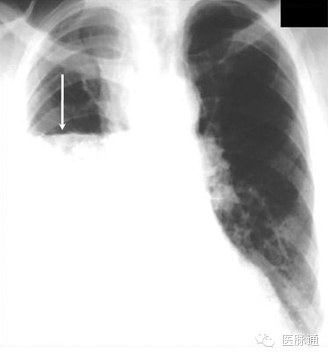

当空气进入到脏层和壁层之间的胸膜腔可发生气胸。原发性自发性气胸的发生无任何潜在肺部疾病和诱发事件,而继发性自发性气胸发生于具有潜在实质性肺疾病的人群(如慢性阻塞性肺疾病,肺纤维化)。胸片中,气胸具有条形阴影,外侧无肺纹理(图2箭头)。气胸最常发生于肺尖,即肺的非重力依赖区。但处于仰卧位的胸片,气胸可能位于肺底或前内侧。比较吸气相与呼气相的胸片可能有助于诊断。

图2